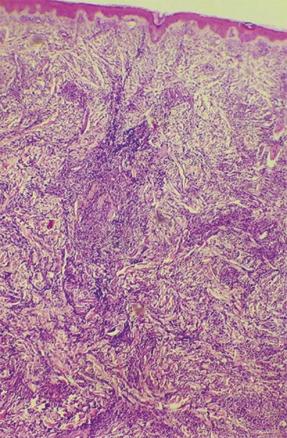

Après concertation pluridisciplinaire, dermatologues et chirurgiens décident d’une biopsie-exérèse. L’étude histologique révèle une infiltration blastique massive (fig. 2) avec expression des antigènes CD20 et CD3, aspect d’une prolifération lymphoïde en faveur d’une leucémie à localisation cutanée.

L’aspect angiomateux et rapidement évolutif du cas présenté a également fait évoquer d’autres diagnostics tels qu’un hémangioendothéliome kapo­siforme, un rhabdomyosarcome, un fibromyosarcome ou une métastase de neuroblastome. La biopsie cutanée est la clé du diag­nostic, objectivant un infiltrat lymphoblastique dermique ; l’immunohistochimie permet de distinguer les leucémies cutanées aleucémiques des troubles lymphoprolifératifs.3